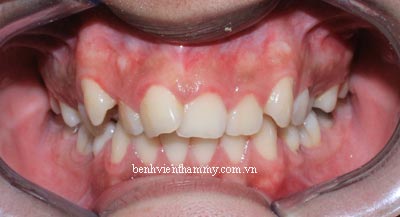

*Bệnh nhân nam 21 tuổi

*Răng mọc khấp khểnh

*Niềng răng có nhổ răng cụ thể là răng : 14,24,35,45

*Niềng răng với mắc cài kim loại Smart Clip SL3-3M-USA

-Thời gian niềng răng 26 tháng

(Hình ảnh trước điều trị)